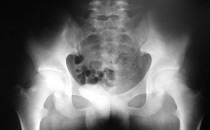

骶骼关节

例子

病症描述:骶髂关节疼痛是类风湿性关节炎的一个症状,特点为隐匿发作、持续钝痛,多发生于活动以后,休息可以缓解。有晨僵和粘着感,随着病情进展,可出现关节挛曲、不稳定、休息痛、负重时疼痛加重。